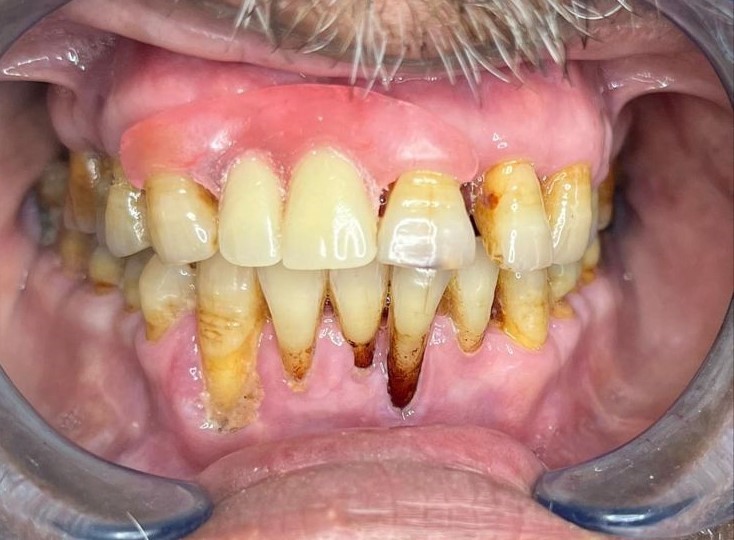

After